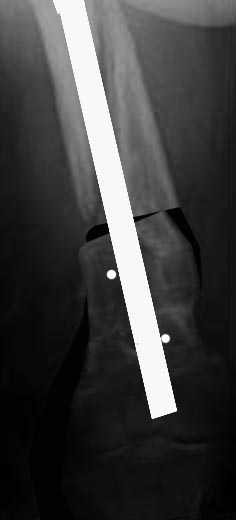

Антеградный канал уже есть, зачем делать еще и ретроградный. Канал

рассверлить и взять гвоздь уже серьезного диаметра, от 12 мм. Но здесь

одна серьезная проблема - вальгус. Наверно (надо скиаграмму сделать и

уточнить) просто измением оси его не устранить, потому что

промежуточный отломок по медиальной стороне сросся с периферическим

под углом, он не даст правильно расположить мыщелки бедра к диафизу.

Для восстановления оси достаточно поперечной остеотомии дистального

отломка по нижнему краю центрального. В периферическом отломке ввести

спереди назад отклоняющие спицы или винты, чтобы гвоздь пошел не по

старому каналу, а куда надо. Приблизительная схемка в приложении.

Гвоздь надо запереть в дистальном отломке более чем 2 винтами. Лучше,

чтобы и винты были потолще.